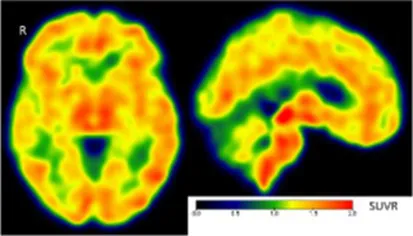

| Clinical findings | CSF and APOE | SWI and T1-weighted MRI scans | Proposition of ongoing neuroinflammatory processes |

| Case 5: a 64 y.o. man who was referred for a memory complaint. At screening, he had 24/30 MMSE and impairment on episodic memory, denomination and categorical verbal fluency tests. On MRI, multiple lobar microbleeds without hemisiderosis were observed as well as WMH (Fazekas’s score of 8/9) and moderate cortical atrophy. | Aβ42: 208 P-tau: 184 T-tau: 1449 APOE E3/E3 TSPO MAB | ![]() | ![]() Toxic neuroinflammation associated with mixed angiopathy and AD pathological progression. |

All fourth patients are right-handed. TSPO PET imaging showed SUVR relative to the cerebellar cortex and is represented in standard space in the same slice and intensity scale, whereas MRI scans are shown in native space. Cerebrospinal fluid AD biomarker values were abnormal for the four patients (see the method section for details).

Aβ42, amyloid-β 42; AD, Alzheimer’s disease; APOE, apolipoprotein E; CAA, cerebral amyloid angiopathy; CSF, cerebrospinal fluid; MMS, mini-mental state examination; MRI, magnetic resonance imaging, P-tau, phosphorylated tau; SWI, susceptibility-weighted imaging; T-tau, total-tau; TSPO, translocator protein; WB, whole brain; WMH, white matter hyperintensities.